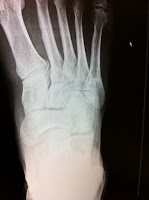

Surgery, thankfully, was completely ruled out as it was evident that the Orthofix was doing it's job nicely and I was on the eventual road to recovery.

I had a safety follow up x-ray just last week and Luke's response summed it all up nicely,

"I'm super impressed by what your body has been able to do here. It looks fantastic."

(left image is late April 2012)

Two thumbs and one healed Jone's Fracture up from this kid. Now bring on the mountains already!!